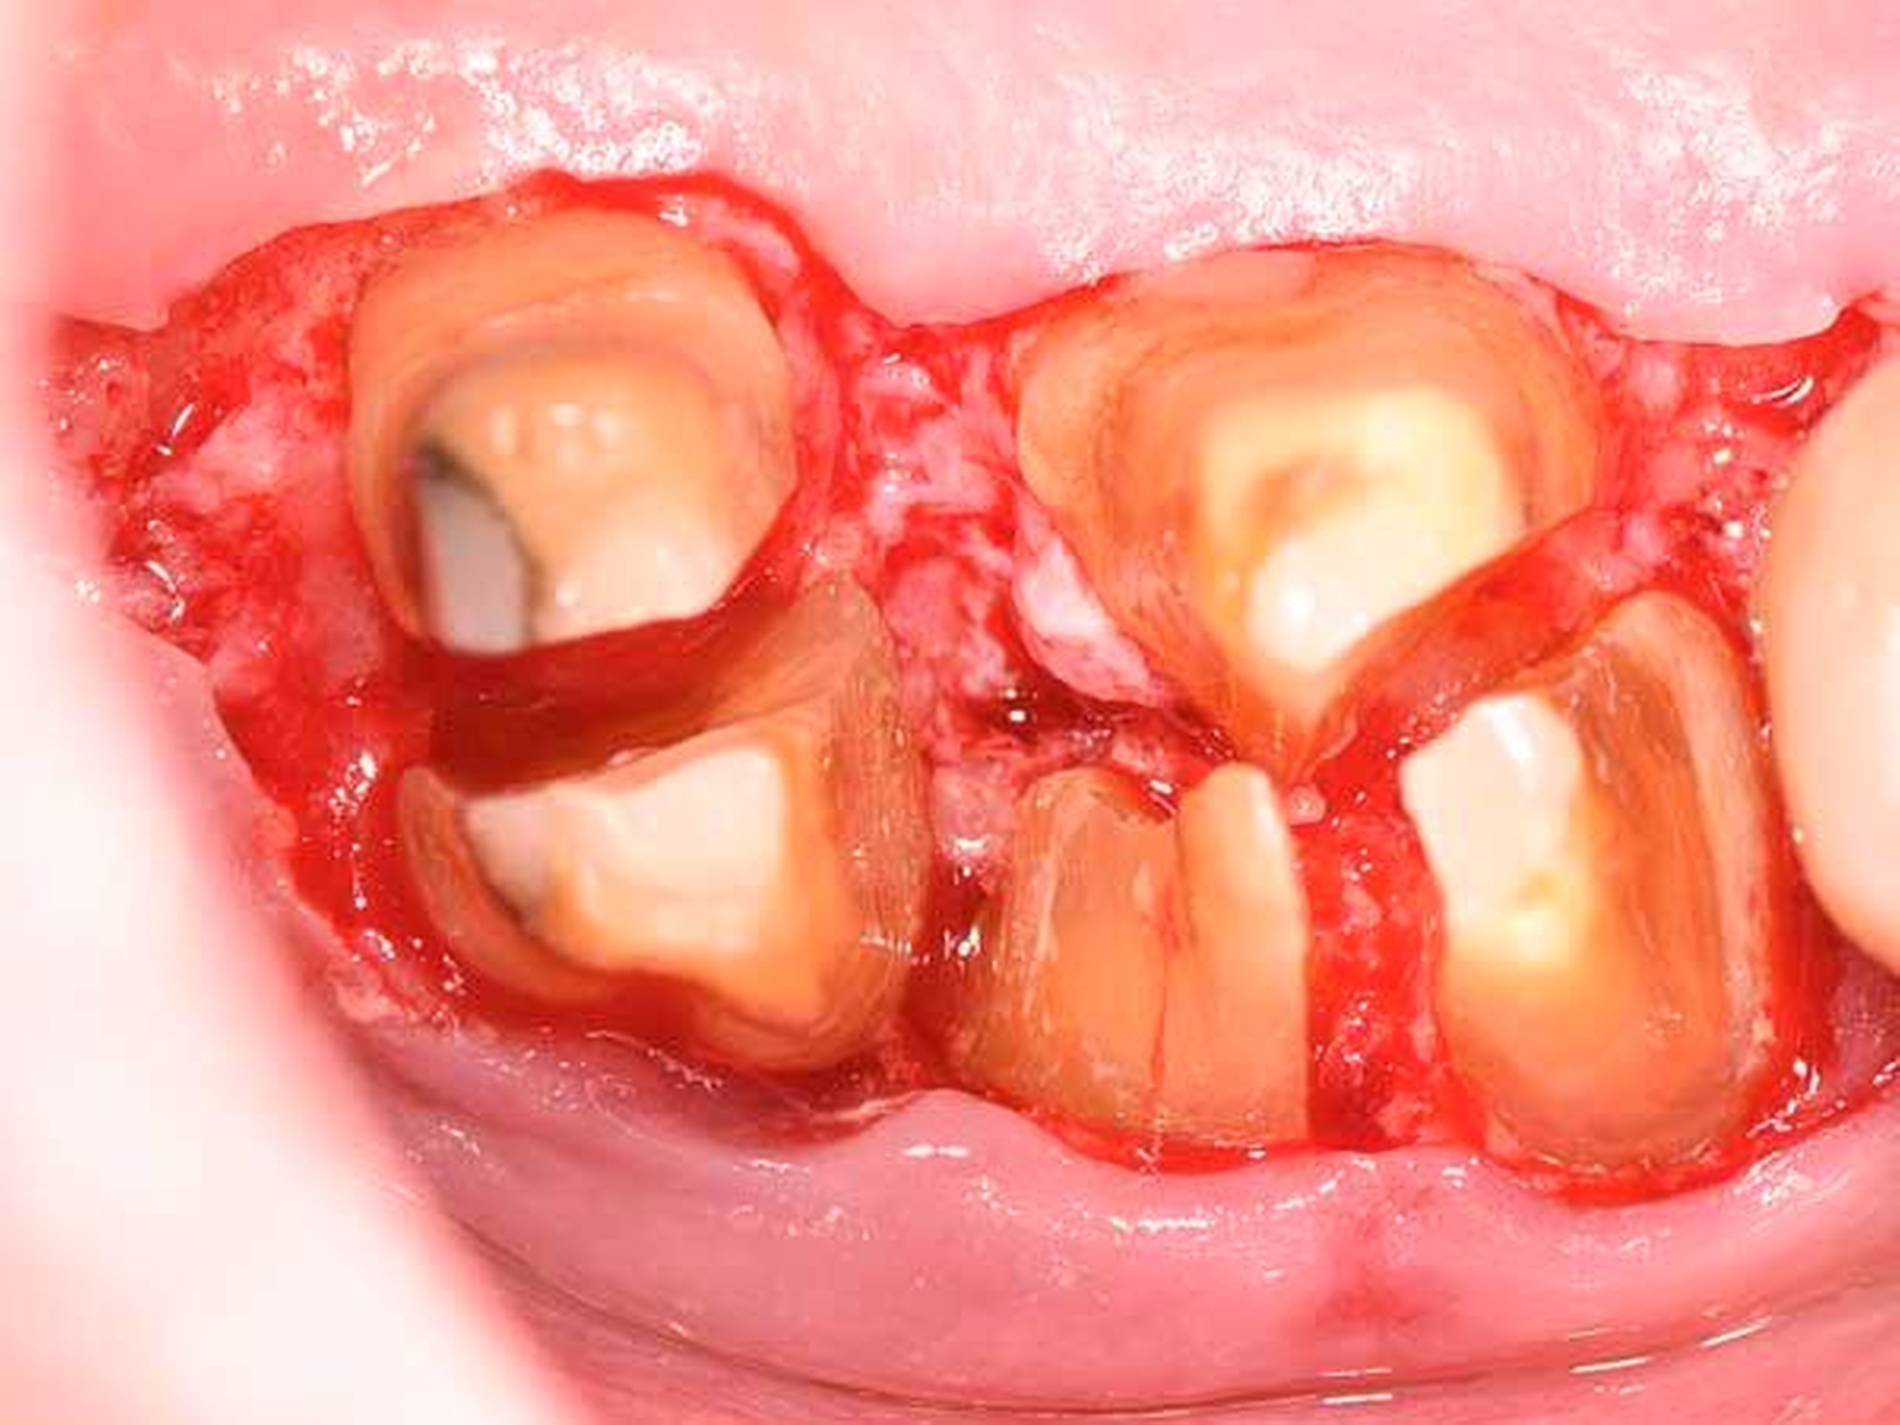

Eine klassische, sehr effiziente und vorhersagbare Möglichkeit der Adressierung von Resttaschen nach der ersten Therapiephase ist die resektive Parodontalchirurgie (Abbildung 5). Mittels eines apikalen Verschiebelappens mit resektiver Knochenchirurgie wird eine positive Gingivaarchitektur mit minimalen Sondierungstiefen auf reduziertem Niveau erschaffen [Carnevale und Kaldahl, 2000; Kebschull und Dommisch, 2013]. Diese Therapieoption wird aufgrund der ästhetischen Einschränkung durch starke Gingivarezession nur in der funktionellen Zone oder präprothetisch (zur Kronenverlängerung) durchgeführt. Die resektive Chirurgie ist bei tiefen Resttaschen ohne einer regenerativen Therapie zugängliche Defekte (siehe unten) indiziert.

Daher gewinnen gerade im posterioren Oberkiefer oder bei Vorliegen einer durchgängigen Furkation resektive Maßnahmen wie die Amputation einer oder mehrerer Wurzeln (Abbildung 8b bis 8d), die Prämolarisierung sowie die Tunnelierung wieder an Bedeutung. Diese Maßnahmen sind klinisch herausfordernd, da neben einer hochwertigen parodontologischen Versorgung eine adäquate endodontologische Therapie und eine sinnvolle restaurative Versorgung für den Langzeiterfolg notwendig sind. Nachdem Autoren aus Italien [Carnevale et al., 1998] und den USA [Fugazzotto, 2001] schon länger von hervorragenden Überlebensraten wurzelamputierter Molaren berichtet haben, liegen nun auch aus Deutschland retrospektive Daten über bis zu 30 Jahre vor, nach denen ein Wurzel-amputierter Molar eine mediane Überlebenszeit von etwa 20 Jahren aufweist [Derks et al., 2017].